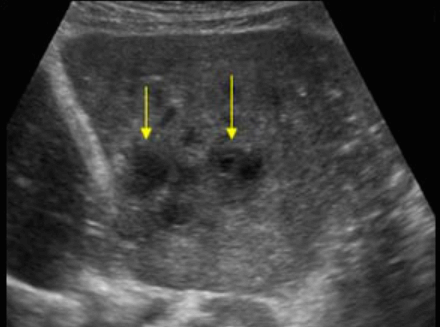

상염색체 우성 다낭성 간질환이라고도 불리는 다낭성 간질환은 유전성 질환이다. 간전체에 흩어져 있는 다양한 크기의 낭종의 점진적인 성장이 특징이다. 이 상태의 영향을 받은 사람들은 나이가 들어감에 따라 점점 더 큰 낭종을 갖는 경향이 있으며 보통 30세부터 증상이 나타나기 시작한다. 그러나 많은 영향을 받은 사람들은 증상이 없다. 대부분의 경우는 상염색체 우성으로 유전되지만, 일부는 가족력이 없는 가정에서도 발생한다. ADPKD를 가진 대부분의 사람들은 간낭종을 가지고 있다.

US finding

- 다양한 크기로 다발성

- 다수 발생 시 간종대 발생

- 60~70% 다낭성 신질환과 동반된다

- 낭종벽에 석회화 동반

- 격막이 형성되어 있다

polycystic liver disease ③ bile duct hamartomas